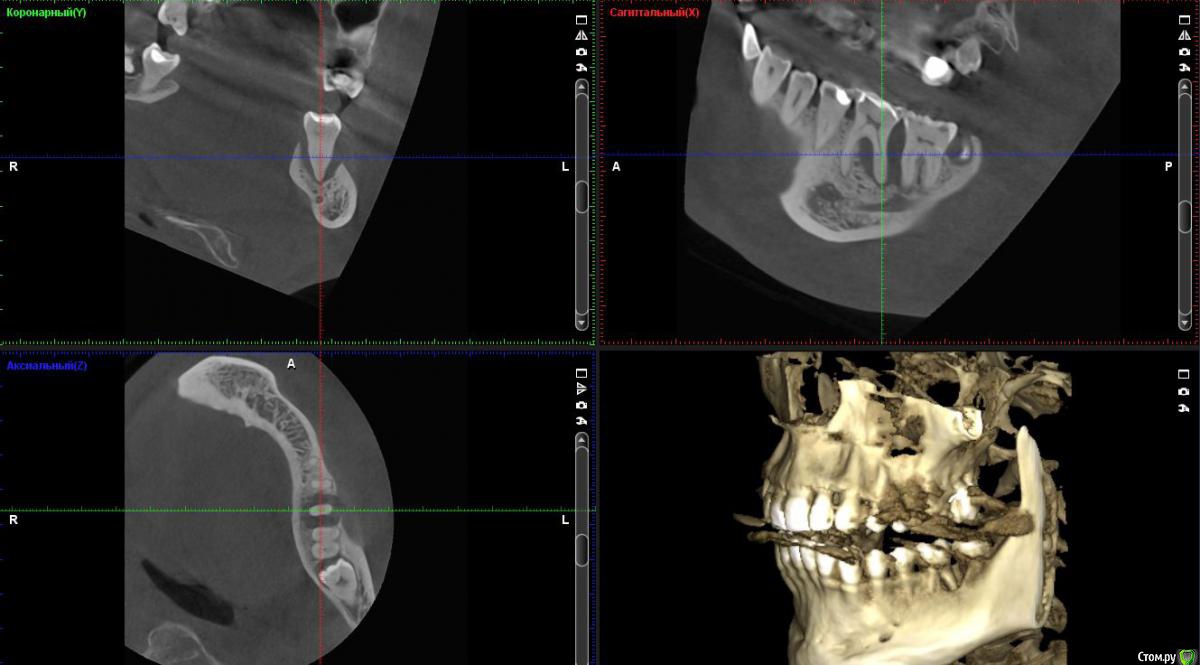

vse32 Опубликовано 20 февраля, 2018 Поделиться Опубликовано 20 февраля, 2018 А меня больше интересует причина такого состояния. И мне кажется, что карман не первичен. Вероятно все началось периодонтитом, долгим и бессимптомным. В таком случае можно было бы попробовать эндо лечение.Но оговорюсь. Эксперимент бы проводила на родственнике - человеке перед которым нет финансовых и юридических обязательств.А так да, самое эффективное и предсказуемое лечение - удаление.Если же первичен пародонтит - то только удаление. Вот бы кто аргументированно доказал первопричину. Ссылка на комментарий

Паращук Роман Опубликовано 21 февраля, 2018 Поделиться Опубликовано 21 февраля, 2018 Если свой,то попробовать эндо через временное вложение и вывести с оклюзии. Через пол-года контрольное кт. Без позитивной динамики переходить к хирургическим этапам. Ссылка на комментарий

Паращук Роман Опубликовано 21 февраля, 2018 Поделиться Опубликовано 21 февраля, 2018 + 1 к удалениюКак быть с мезиальным корнем 7ки? Ссылка на комментарий

red_butler Опубликовано 21 февраля, 2018 Поделиться Опубликовано 21 февраля, 2018 Как быть с мезиальным корнем 7ки?про седьмой и восьмой, я скромно умолчал. Надо очно смотреть. но прогноз седьмого - плохой Ссылка на комментарий